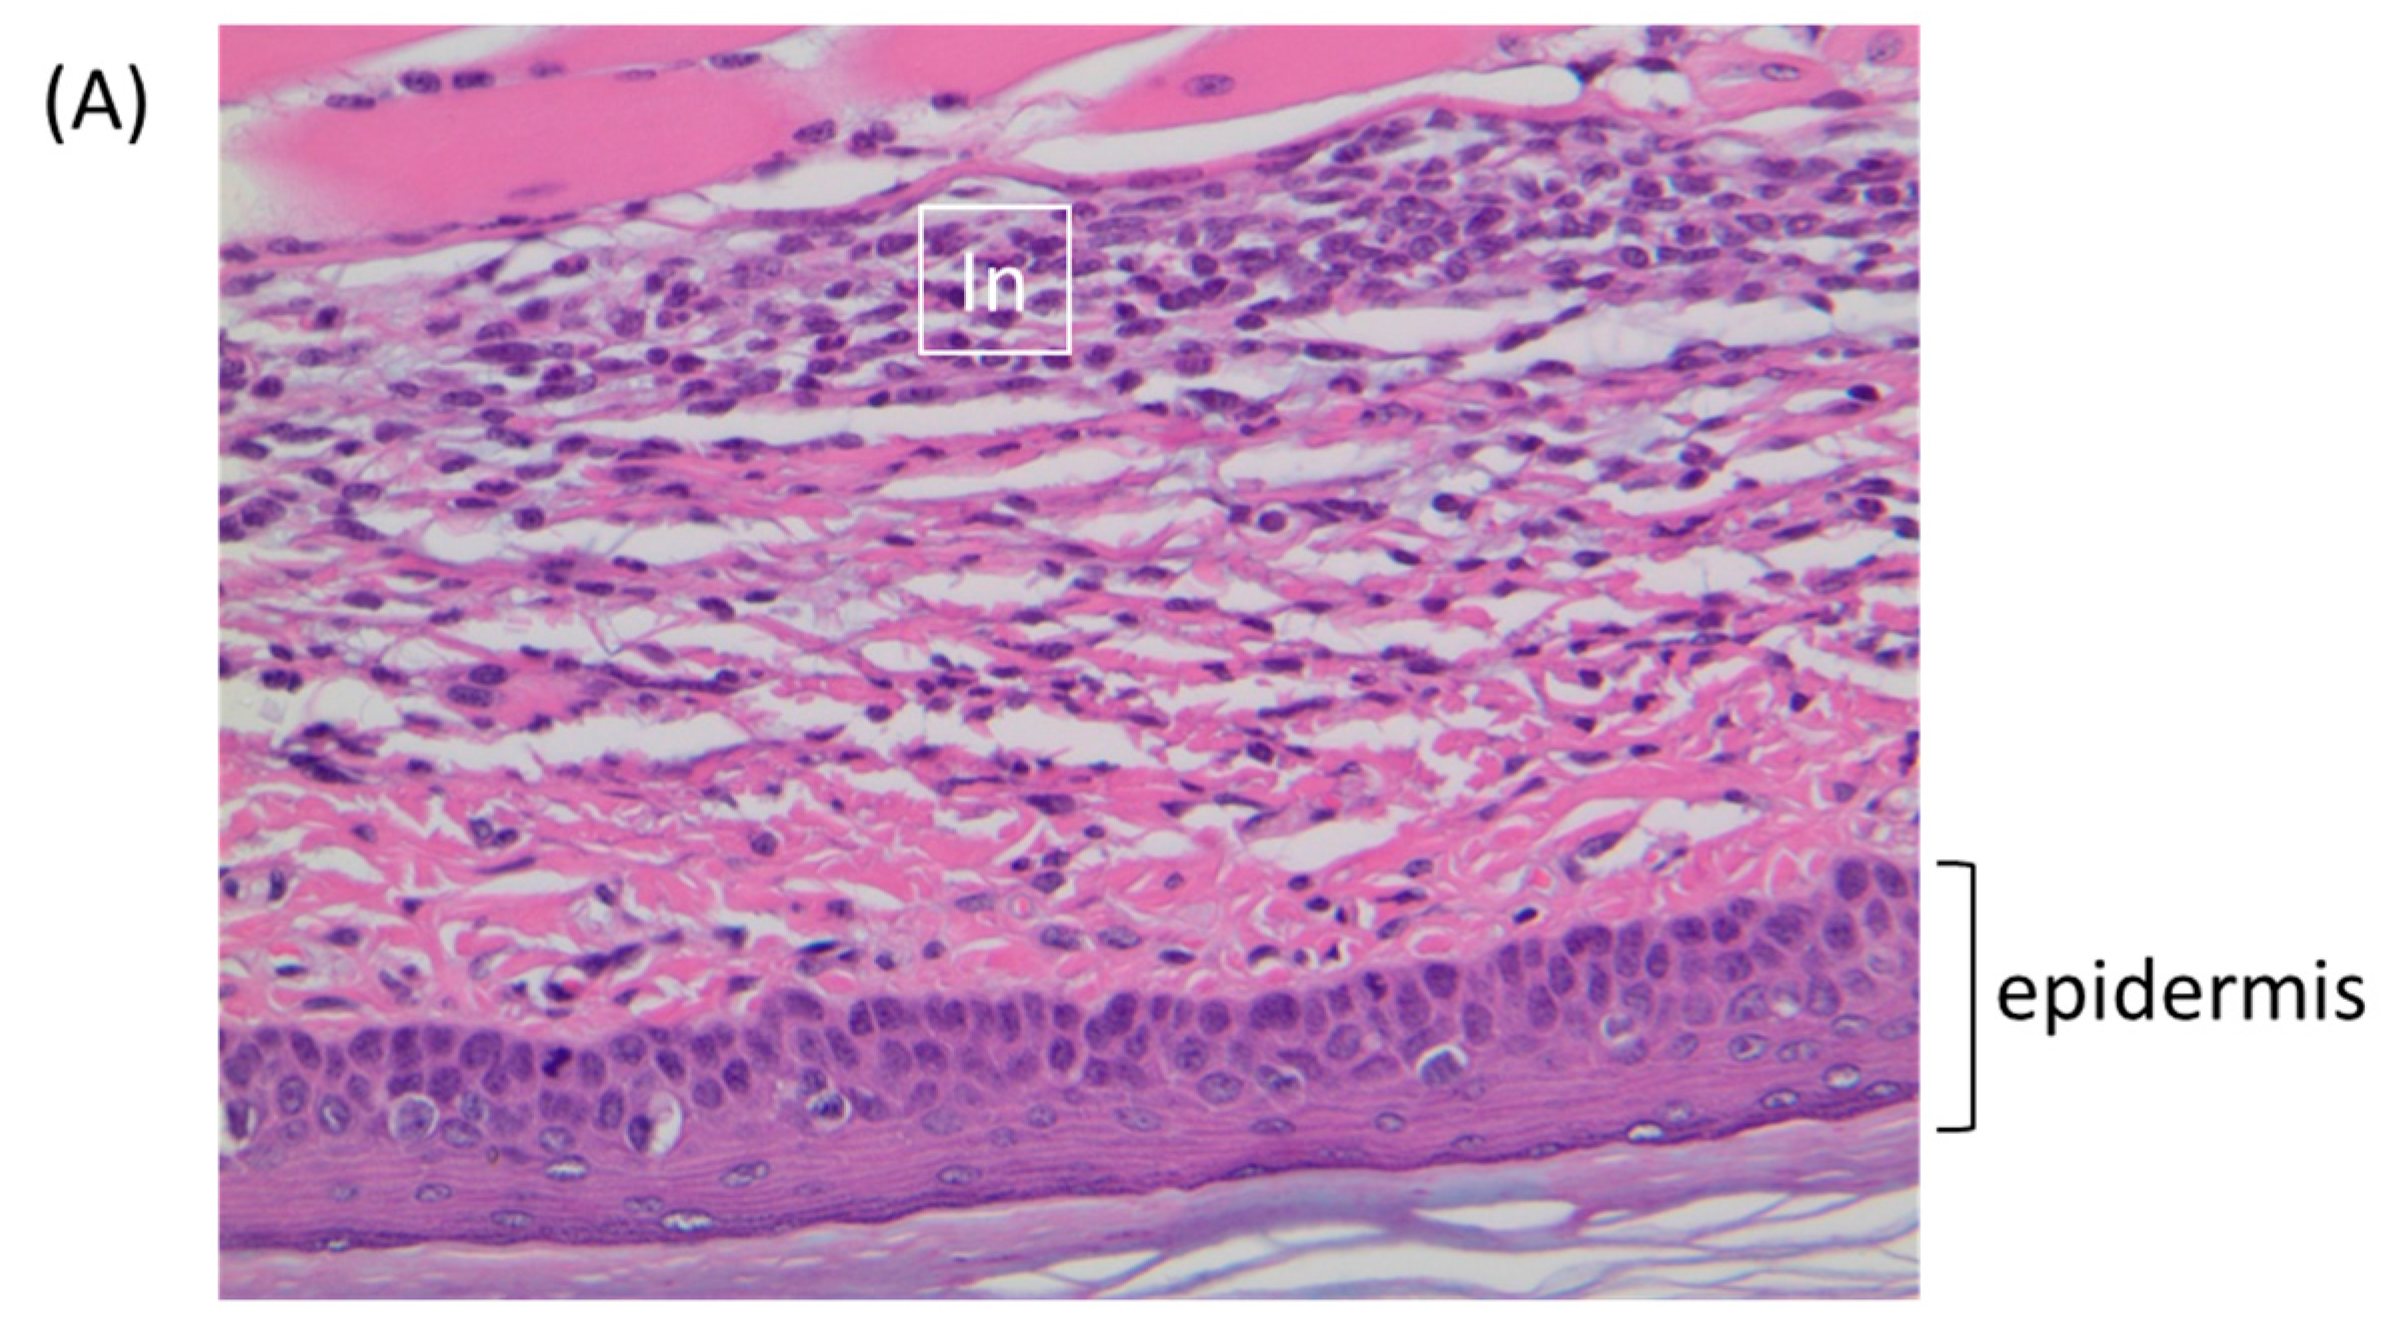

3.7. The Host Response at the Draining Lymph Node

| TATV | Inflammation, subacute | MF | 2 | 4 | Plantar metatarsal region |

| Inflammation, subacute | MF | 3 | 2 | Plantar metatarsal region | |

| ECTV | Inflammation, subacute | MF | 1 | 5 | Plantar metatarsal region |

| Inflammation, subacute | MF | 1 | 1 | Plantar metatarsal region and periosteal (distal tibia) |